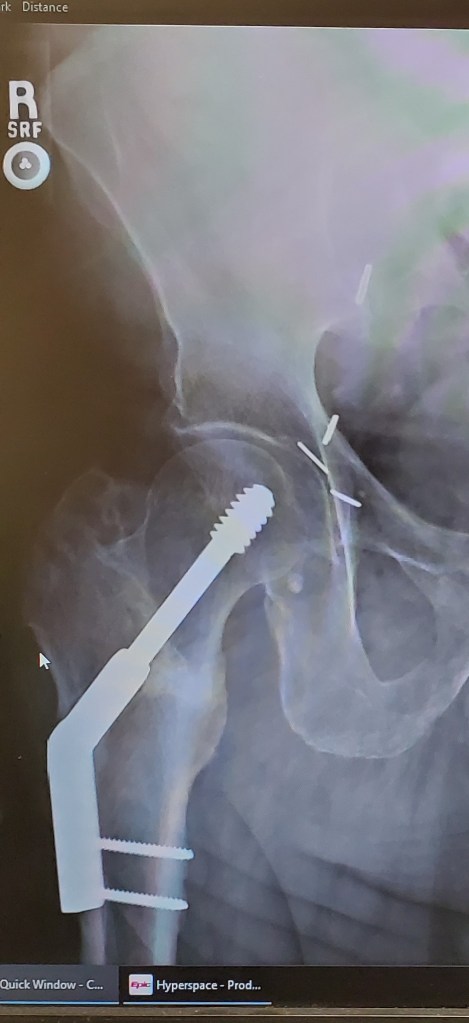

It seemed like an ordinary Fall Day at the lake. I had returned from lunch and was walking to the RV when I fell. I heard the snap as my knees hit the ground. I broke my leg (femur). I was by myself, lying in the slow falling rain. In the past, I had ridiculed the commercial “I’ve fallen, and I can’t get up!” I’m a big old boy, that could never happen to me, but now I could not even drag myself to a dry area. Mary came shortly but she was not able to move me. Little did I know that God was preparing to teach me a significant Prayer Principle. This was a God School’s Lab Session, that taught me about praying God’s transforming power.

An hour later the ambulance came, picked me up and transported me to Conway Baptist ER. After the medical team assessed my injuries and prepped me for my room, Pastor Randy Jumper, from our church, came to check on me and pray. This was the pivotal moment. He ended his prayer with, “and that others will see Jesus through Robert’s experience.” I didn’t think much about this until the next morning as I was thanking the housekeeping lady for the great job she was doing, she began tear up and said, “No one ever thanks me.” Bam! I remembered Pastor Randy’s prayer and knew if had I not broken my leg, I would have never met this lady. Pastor Randy’s prayer changed my focus from me to Jesus…from my pain to the Joy of Blessing others. It seemed my broken leg brought people to me to Bless. One day at Rehab people lined up outside my door to see me…to tell how Jesus will Bless them. Then God blew me away. He paired me up with a therapist that proclaimed she was an atheist. Only God does this…she had to help me walk, supporting me for an hour each day as I talked to her about The Hope…The Promise…The Freedom of Jesus. I am thankful for my broken leg. I am thankful for Pastor Randy’s Prayer Principle, “In every situation, people should see Jesus through us!”